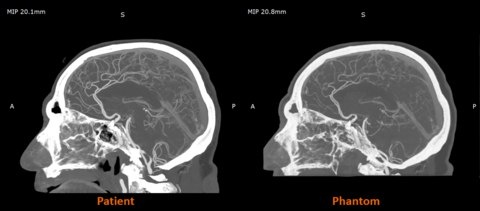

Stratasys выводит на рынок США материал RadioMatrix для PolyJet-принтеров. Его ключевая особенность — возможность точно настраивать рентгеноконтрастность, имитируя плотность кости, жира или сосудов. 🩻

На сканах такие модели отклоняются от реальных тканей всего на 1 единицу Хаунсфилда! Это революция для обучения радиологов и тестирования медоборудования, предлагающая повторяемую и масштабируемую альтернативу дорогим кадаврам и ограниченным фантомам.